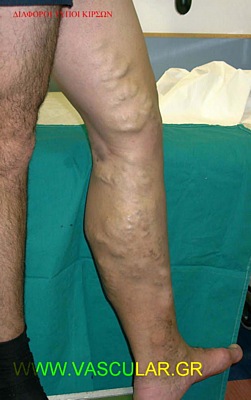

Ïé êéñóïß åßíáé åêôåôáìÝíåò äéåõñõíóìÝíåò öëÝâåò ìå âáëâßäåò ðïõ äåí ëåéôïõñãïýí óùóôÜ . ÁõôÞ ç äéåýñõíóç ðñïêáëåß öëåâéêÞ ðáëéíäñüìçóç ,êÜíïíôáò ôá ôïé÷þìáôá áäýíáìá

Ïé öëÝâåò óôçí åðéöÜíåéá ôïõ äÝñìáôïò ðáñïõóéÜæïíôáé áíôéáéóèçôéêÝò êáé äéïãêùìåíåò.

ÊáôÜ ôçí ÷åéñïõñãéêÞ èåñáðåßá ç ïðïßá áöïñÜ ôïõò ðñùôïðáèåßò êéñóïýò óõíßóôáôáé ç üóï ôï äõíáôüí ðëÝïí ñéæéêÞ áöáßñåóç ôùí êéñóüåéäþí áíåõñýíóåùí êáé áëëïéùìÝíùí óôåëå÷þí ôçò ìåßæïíïò êáé åëÜóóïíôïò óáöçíïýò öëåâüò êáé êëÜäïõò áõôþí. Ïé êõñéþôåñåò åíäåßîåéò ðåñéëáìâÜíïõí ôïõò åõìåãÝèåéò óõìðôùìáôéêïýò êéñóïýò, , .Ôá åðåéóüäéá åðéðïëÞò öëåâéêÞò èñïìâþóåùò , ç ýðáñîéò áíåðáñêþí äéáôéôñïõóþí öëåâþí êíÞìçò ìåôÜ ôñïöéêþí áëëïéþóåùí , ìåôÜ Þ áíåõ åîåëêþóåùí êáé ôÝëïò ãéá áéóèçôéêïýò ëüãïõò.